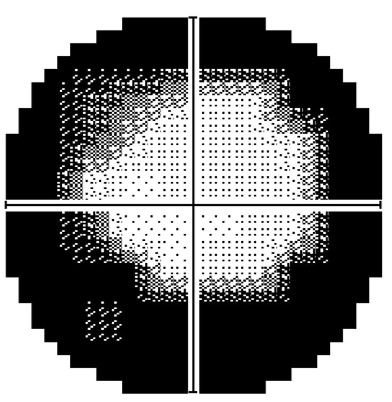

More infoHumphrey 10-2 threshold visual field analysis

More info